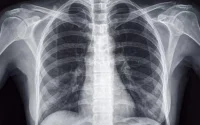

Aux États-Unis, un garçon marocain né « sourd profond », en raison d’une anomalie très rare, présente sur un seul gène, a subi une intervention chirurgicale qui a connu un franc succès. Une première dans le pays.

Un espoir pour les patients du monde entier souffrant d’une perte d’audition causée par des mutations génétiques. Suite à une intervention chirurgicale consistant à soulever partiellement son tympan, puis à injecter dans le liquide interne de sa cochlée un virus inoffensif qui avait été modifié pour transporter des copies fonctionnelles du gène de l’otoferline le 4 octobre 2023, Aissam Dam, un garçon né au Maroc, entend désormais les bruits qui l’entourent. Un succès enregistré après presque quatre mois de traitement. « Il n’y a pas un son que je n’aime pas », s’est réjoui le patient auprès du New York Times, avec l’aide d’interprètes, lors d’une interview la semaine dernière. « Ils sont tous bons », a-t-il ajouté.

« La thérapie génique pour la perte auditive est un objectif que nous, médecins et scientifiques de la perte auditive, poursuivons depuis plus de 20 ans. Et nous y sommes enfin arrivés », a déclaré le chirurgien John Germiller, directeur de la recherche clinique dans la division d’oto-rhino-laryngologie (ORL) à l’hôpital pour enfants de Philadelphie (CHOP), qui a réalisé le traitement dans un communiqué publié mardi. Et de se féliciter : « La thérapie génique que nous avons appliquée à notre patient visait à corriger l’anomalie d’un gène très rare, mais ces études pourraient ouvrir la voie à une utilisation future pour plus de 150 autres gènes responsables de la perte auditive chez l’enfant ».

Si celui qui a déménagé en Espagne avec sa famille ne souffre plus que d’une surdité légère, il a en revanche moins de chance de parler. « Il pourrait toutefois ne jamais pouvoir parler, la partie du cerveau destinée à l’acquisition de la parole se fermant vers l’âge de cinq ans », fait savoir le quotidien new-yorkais. Aissam Dam a 11 ans.